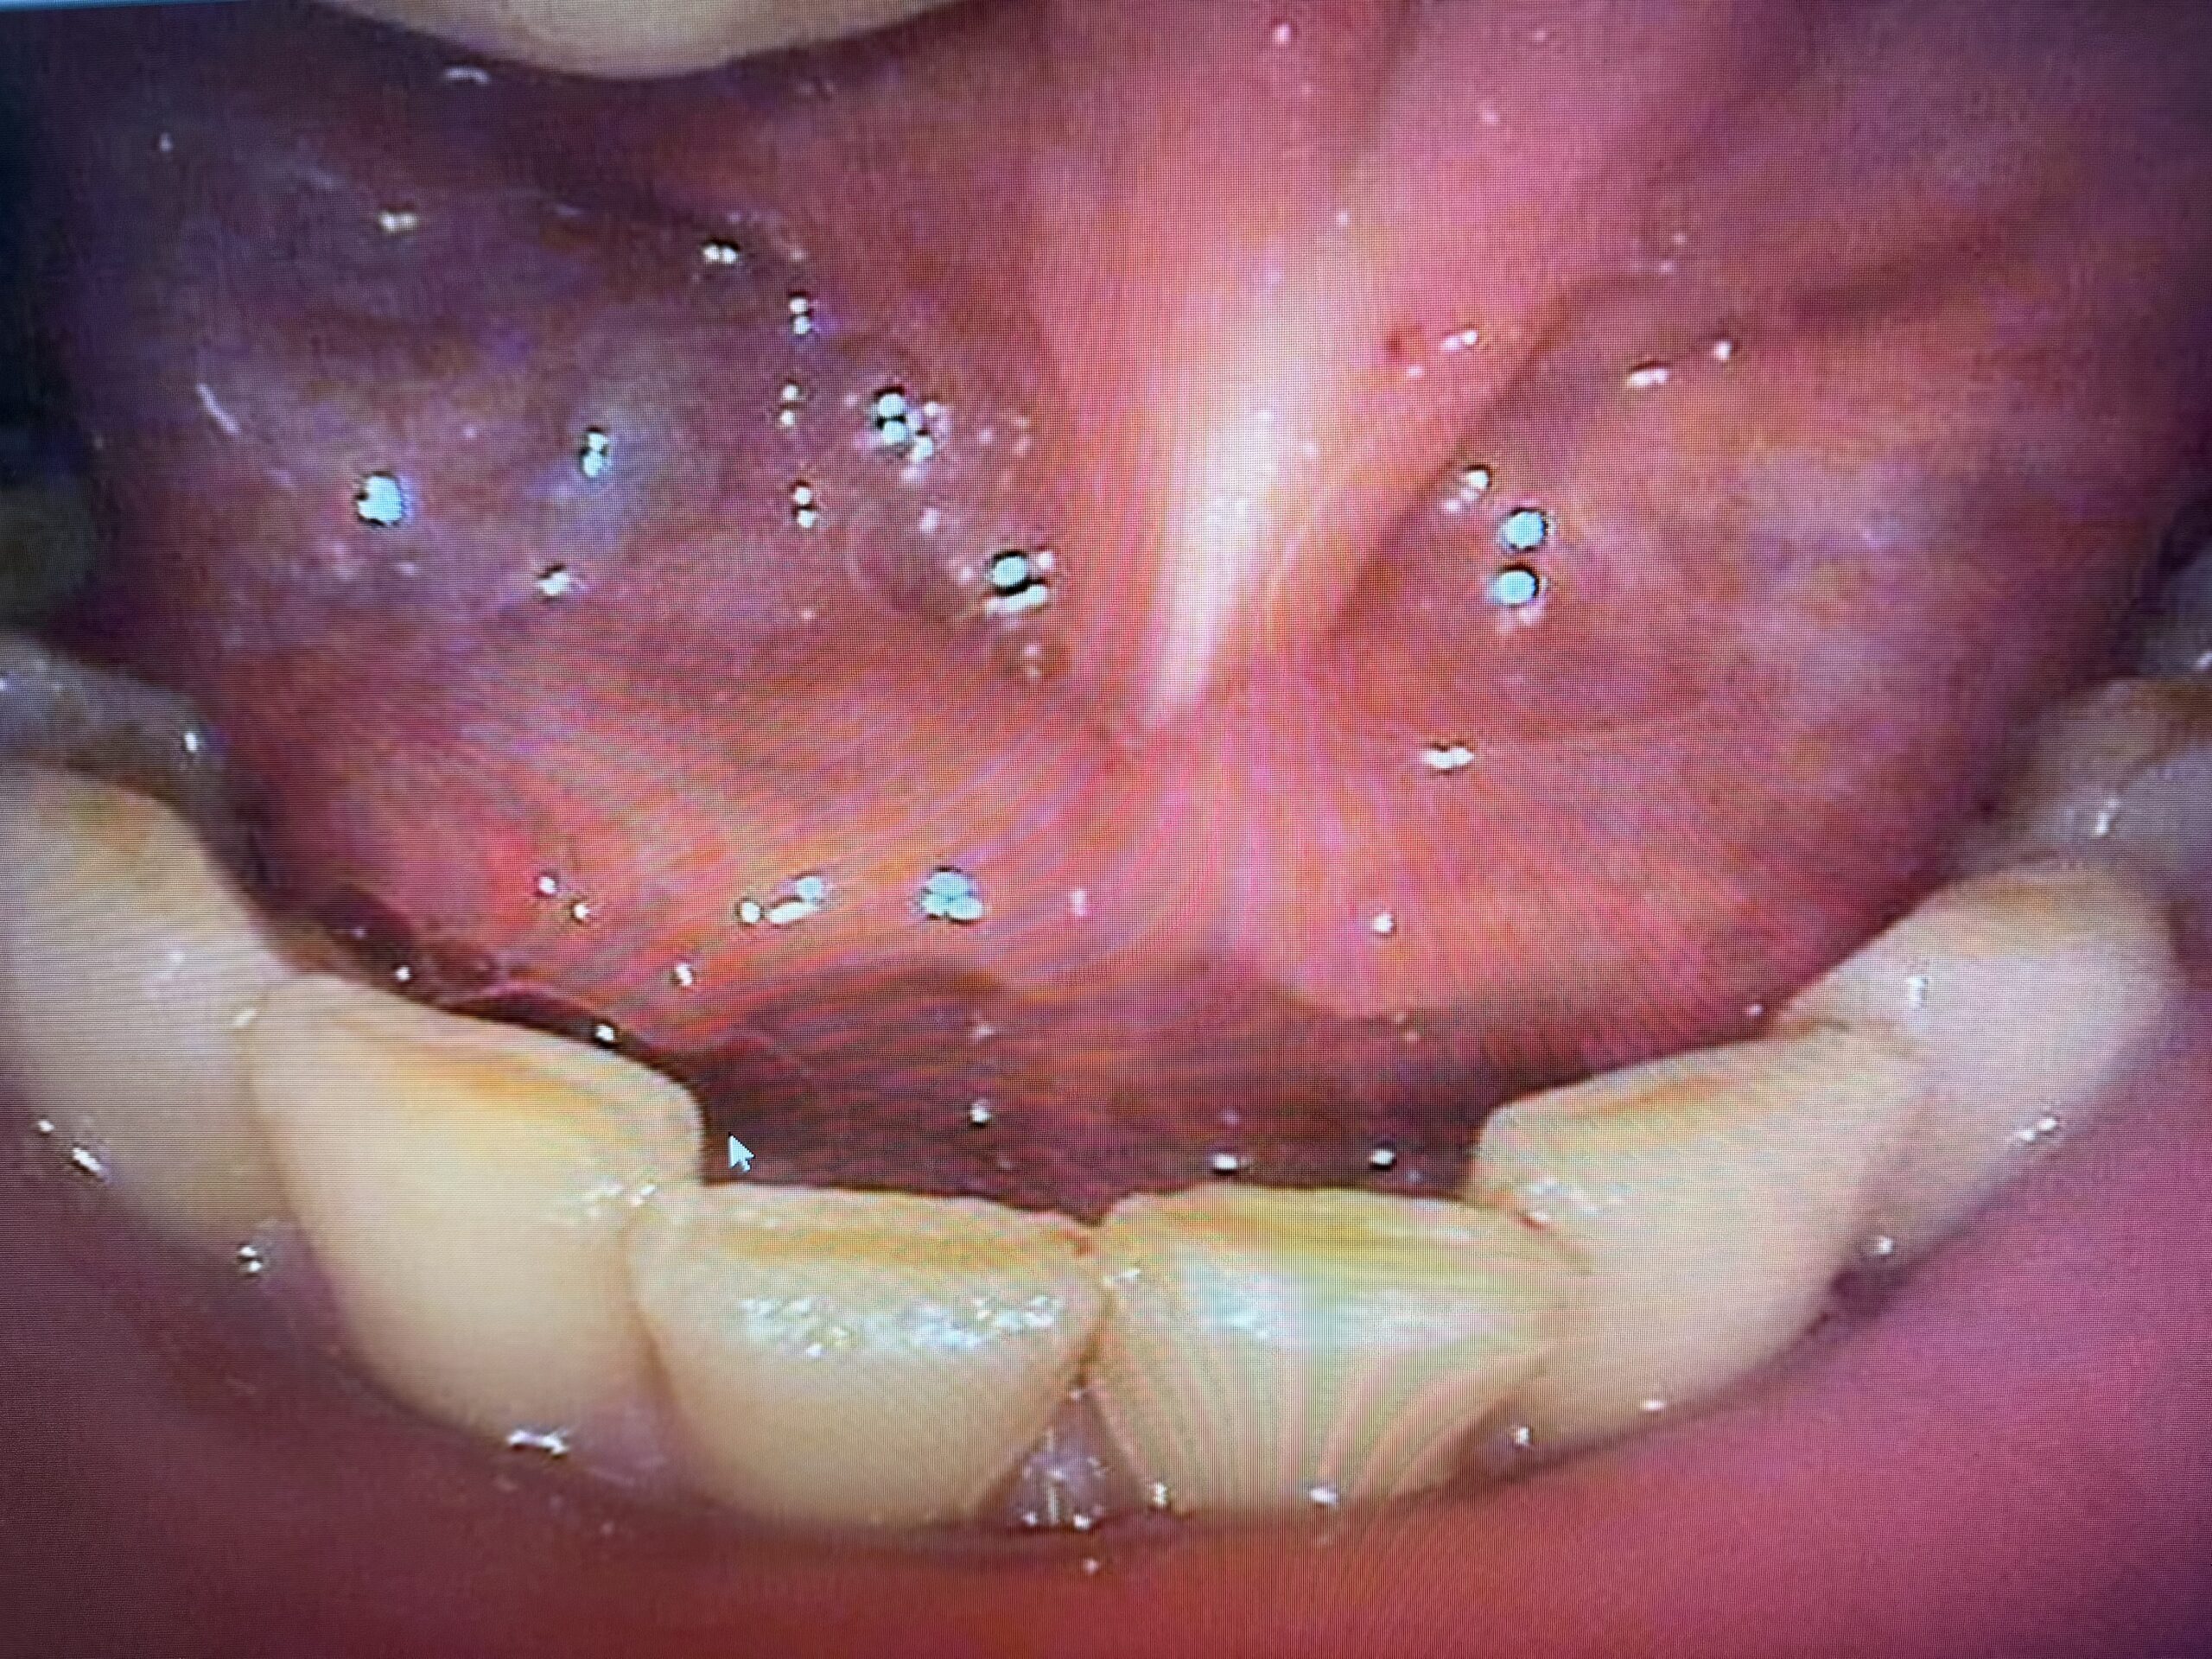

舌小帯短縮症の治療例

IMG_9748